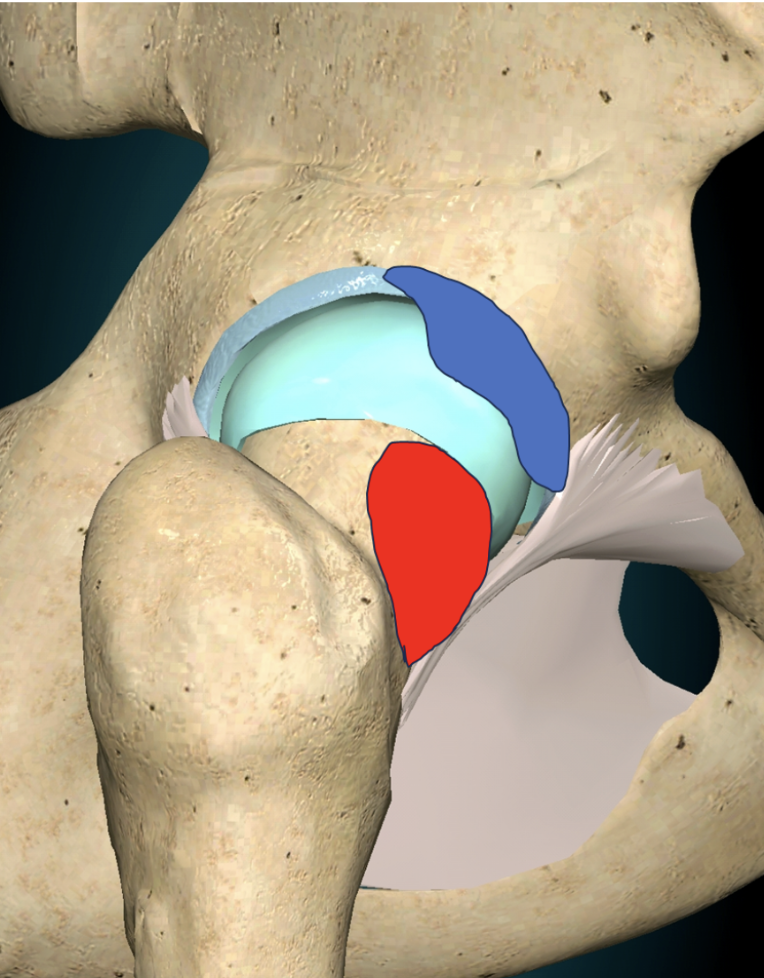

Le conflit fémoro-acétabulaire (CFA) est une pathologie de la hanche caractérisée par une interaction anormale entre la tête du fémur et l’acétabulum, la cavité de l’os du bassin où la tête du fémur s’articule. Cette pathologie peut causer des douleurs à la hanche, une raideur articulaire, et potentiellement des lésions du cartilage et de l’os. Si non traitée, elle peut conduire à la coxarthrose, une forme d’arthrose de la hanche.

- Type à came : Caractérisé par une bosse sur le col du fémur, ce type entraîne un contact précoce des structures osseuses lors des mouvements de la hanche.

- Type à pince : Ce type est dû à une déformation de l’acétabulum, entraînant un contact osseux précoce similaire.

Le conflit fémoro-acétabulaire, également connu sous le nom de conflit antérieur de la hanche, se réfère à une interaction anormale entre la cavité de l'os du bassin et le col du fémur pendant les mouvements de hanche. Cette interaction peut causer des dommages au cartilage et au labrum, provoquant douleurs et limitations de mobilité.